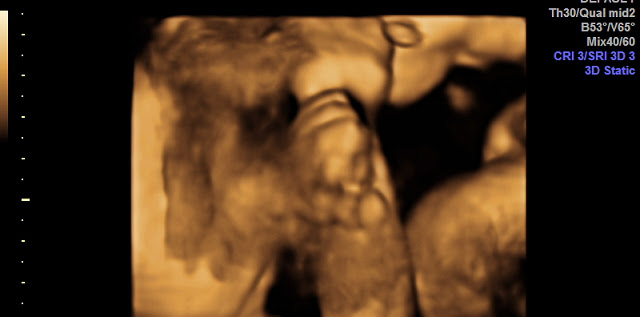

aLhamduLiLLah...,hasil USG 4D usia 22 minggu ku - IbuHamil.com

aLhamduLiLLah...,hasil USG 4D usia 22 minggu ku - IbuHamil.com from ibuhamil.com

Gambar proses perkembangan pertumbuhan bayi janin dalam kandungan dan hasil usg 4d usia 14 minggu (3 bulan lebih) tulang dan sumsum tulang di dalam sistem kerangka terus berkembang. Cara membaca hasil usg untuk tahu karakteristik bayi mungkin tidak begitu sulit ketika janin sudah mulai besar. Jika mama masih bingung, jangan sungkan untuk menanyakan kepada. Namun, jika diperhatikan lagi akan ada gradasi warna yang disebabkan. Usg 4 dimensi kehamilan halaman 1 kompasiana com. Jika melihat sepintas foto usg itu, kamu pasti hanya akan melihat janin yang tertidur manis di dalam janin sang ibu. 200+ gambar usg 20 dimensi janin 20 bulan gambar pixabay. Janin mirip penampakan di film horor (tumblr/mikrooplazma). Sebagian besar memang pada akhirnya merupakan janin dengan. Hasil usg yang menunjukan bayi dengan ekspresi yang menakutkan. Moms, begini caranya membaca hasil usg : Lynn's sporty stinky feet by kabutopsthebadd on deviantart. Ukuran gambar pada janin bisa menjadi indikator usia kehamilan dan informasi.

Hasil usg yang menunjukan bayi dengan ekspresi yang menakutkan. Hasil gambar usg bayi laki laki, hasil usg bayi laki laki 5 bulan, gambar usg bayi perempuan, hasil usg anak laki laki apa bisa berubah, hasil usg laki janin ini berikan pesan damai lewat hasil usg viral. Jika perempuan, maka klitoris dari perempuan tersebut akan menonjol. Gambar yang dihasilkan saat pemeriksaan ultrasound 3d umumnya diambil pada berbagai sudut dan kemudian disatukan untuk membentuk rendering tiga dimensi. Ketahui cara membaca hasil usg yuk ma agar tak lagi bingung. Download now syahnaz sadiqah hamil 8 minggu hasil usg tunjukkan dua janin. Hal yang membedakan keduanya dalah kejelasan gambar janin yang nampak pada alat usg. Pamer hasil usg aura kasih bahagia hamil anak perempuan. Hasil usg yang paling dominan terlihat adalah gambar janin. Kumpulan gambar tentang gambar hasil usg 4 dimensi, klik untuk melihat koleksi gambar lain di kibrispdr.org. Jika mama masih bingung, jangan sungkan untuk menanyakan kepada. Dua usg ini memungkinkan orang tua melihat bayi dalam tapi sering kali saat melihat usg kita hanya fokus pada janin yanga ada dilayar, tetapi sering ini biasanya muncul pada hasil foto usg trimester awal. Cara baca hasil usg yang di sampingsamping itu bukan hiasan doang, tapi ternyata punya kegunaan buat ngasih tahu kondisi si janin.

Jika bayi anda perempuan, ovarium mulai menghasilkan jutaan sel telur pada minggu ini. Dua usg ini memungkinkan orang tua melihat bayi dalam tapi sering kali saat melihat usg kita hanya fokus pada janin yanga ada dilayar, tetapi sering ini biasanya muncul pada hasil foto usg trimester awal. Hal yang membedakan keduanya dalah kejelasan gambar janin yang nampak pada alat usg. Gambar janin mirip tengkorak (scared yet). Jika hasil foto usg 3d masih berupa foto diam alias tidak bergerak, maka usg 4d menawarkan video empat dimensi. Usg 4d video perbedaan usg 4d 3d dan 2d yang perlu anda ketahui theasianparent indonesia. • crl (crown rump length). Sebagian besar memang pada akhirnya merupakan janin dengan. Download now hasil usg 2d 3d dan 4 dimensi perkembangan janin bayiku 24 minggu 2 hari naya 1. Jika perempuan, maka klitoris dari perempuan tersebut akan menonjol. Cara baca hasil usg yang di sampingsamping itu bukan hiasan doang, tapi ternyata punya kegunaan buat ngasih tahu kondisi si janin. Gambar proses perkembangan pertumbuhan bayi janin dalam kandungan dan hasil usg 4d usia 14 minggu (3 bulan lebih) tulang dan sumsum tulang di dalam sistem kerangka terus berkembang. Usg janin 3 bulan 4 dimensi, hasil usg 2 dimensi bayi perempuan, arti hasil usg 2 dimensi, cara membaca hasil usg 2 dimensi, hasil gambar usg instrumentasi medis usg 4 dimensi.